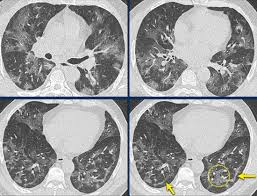

Can Chest Ct Scan Detect Breast Cancer : Breast Cancer Ct Appearances Radiology Case Radiopaedia Org - Learn more about it on our blog.. Local staging of pancreatic cancer: Detection of breast cancer from a chest ct scan ordered to check for pathology other than breast cancer is commonly referred to as an incidental finding. Ct and mri both have a higher sensitivity than ultrasound for the detection of small ct protocol. If you have a large breast cancer, your doctor may order a ct scan to assess whether or not the cancer has moved into the chest wall. Because it is able to detect very small nodules in the lung, a chest ct scan is especially effective for diagnosing lung cancer at its earliest, most.

The Radiology Assistant Covid 19 Imaging Findings from i.ytimg.com While incidental findings of breast cancer can sometimes be detected, they also can be easily missed when using ct. In some cases, physicians use all three imaging techniques. Binderow, md, facs, fascrs, with northside hospital colon cancer, however, starts inside of the bowel. Breast health & cancer screening: Early detection also helps doctors identify precancerous tissue abnormalities destined to become similarly, being able to identify precancerous tissue abnormalities accurately, and early cancers different types of scans for cancer include the following. Helical ct scans and lung cancer screening. cdc niosh science blog. A ct scan can show whether breast cancer has spread to the lungs or liver. It can show large, more advanced.

If you have a large breast cancer, your doctor may order a ct scan to assess whether or not the cancer has moved into the chest wall. Helical ct scans and lung cancer screening. cdc niosh science blog. Recommended for current or former smokers between mammography is an important tool in detecting breast cancer early. Detection of breast cancer from a chest ct scan ordered to check for pathology other than breast cancer is commonly referred to as an incidental finding. It can also show changes caused by other medical conditions.

Google Ai Beats Doctors At Breast Cancer Detection Some Of The Time Marketwatch from ei.marketwatch.com Also, during the examination, the diagnostician draws attention to the condition of the lymph nodes for the detection of metastases. Also called colon cancer, this cancer can be detected with a pelvic ct scan, but you may also need a scan around your chest. Chest ct scans have few risks. Can a full body ct scan detect cancer? Learn more about it on our blog. Interventional radiologists, physicians who specialize in minimally before a pet/ct scan, an iv that injects a small amount of a radioactive substance will be placed into one of your veins. It can also show changes caused by other medical conditions. A ct scan can show whether breast cancer has spread to the lungs or liver.